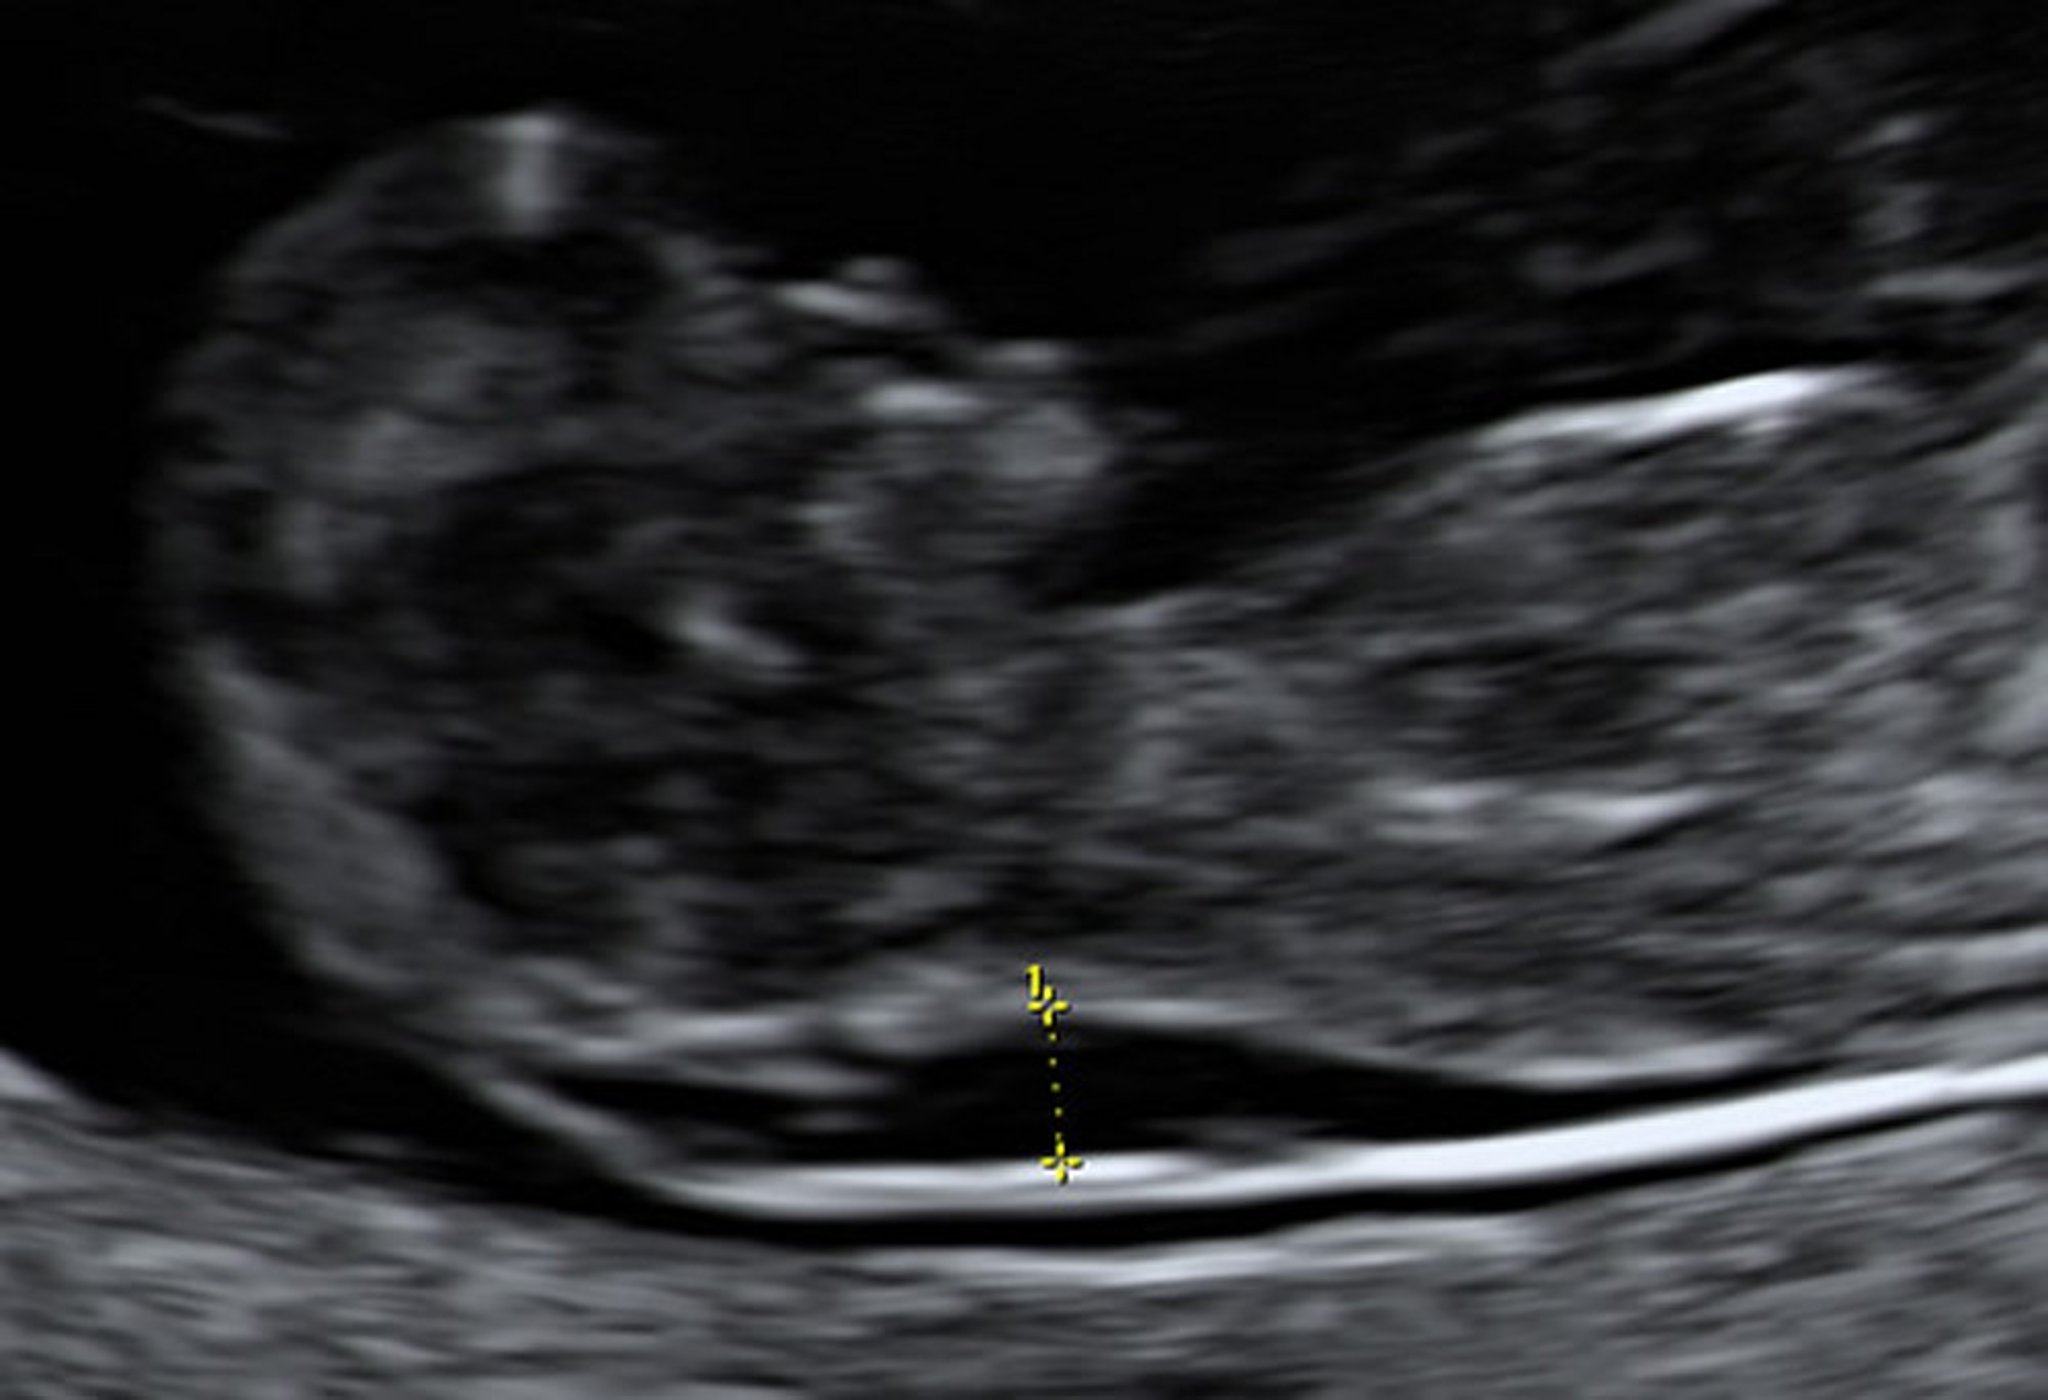

10週の胎児のNT肥厚を示す超音波所見

絨毛採取でこの胎児がダウン症候群であることが示された。

Photo from Jeffrey S.Dungan, MD.